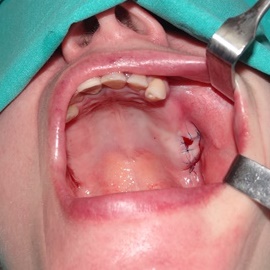

Brakujących pięć zębów dolnych w odcinku wargowym. Rekonstrukcja tkanek i rehabilitacja protetyczna.

Skrócony łuk zębowy, kończący się na trójce. Blade atroficzne tkanki miękkie, relif dziąsła typu A, kość o małej gęstości, słabo ubeleczkowana i o kiepskim ukrwieniu. Niekorzystne warunki do odbudowy kości. Okres leczenia 1,5 roku, po odbudowie kości, zadowalający wynik końcowy w żuchwie, czas na korektę płaszczyzny zgryzowej.

Implantacja natychmiastowa. Zęby paradontyczne. Usuniete zgodnie z popularną obecnie na zachodzie techniką: usuń zęby zanim zaniknie kość. Wynikiem takiego postępowania jest mniejsza trauma dla pacjenta i krótszy okres trwania rehabilitacji protetycznej, niższe całkowite koszty leczenia. Ale jednocześnie więcej implantów i mniej własnych zębów. W długotrwałym okresie obserwacji takie podejście daje dobre wyniki.